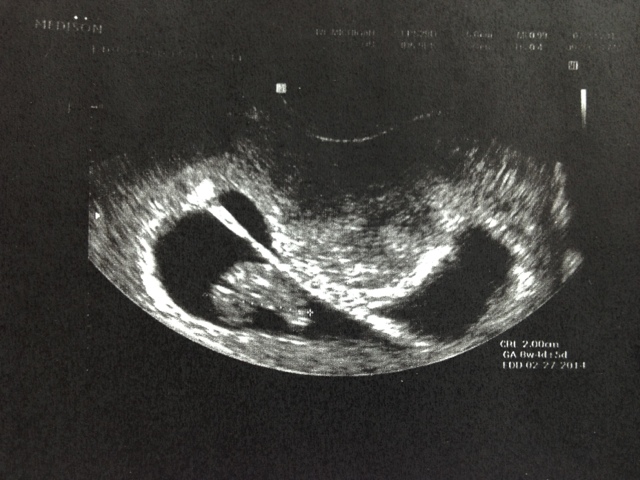

Last Monday we had our 8 1/2 week US and everything is right on track. The babies are growing like they should and their placentas, cords, and heartbeats look fantastic! We both had to go to work immediately after. After work we both went to Babies R Us and geeked out at all the baby stuff. We purchased a handful of things in order to 'break the news' to my parents.